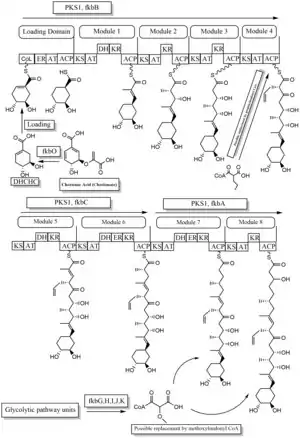

The biosynthesis of tacrolimus is hybrid synthesis of both type 1 polyketide synthases (PKS 1) and nonribosomal peptide syntheses (NRPS). The research shows the hybrid synthesis consists of ten modules of type 1 polyketide synthase and one module of nonribosomal peptide synthase. The synthetic enzymes for tacrolimus are found in 19 gene clusters named fkb. The 19 genes are fkbQ, fkbN, fkbM, fkbD, fkbA, fkbP, fkbO, fkbB, fkbC, fkbL, fkbK, fkbJ, fkbI, fkbH, fkbG, allD, allR, allK and allA.[53]

There are several possible ways of biosynthesis of tacrolimus. The fundamental units for biosynthesis are following: one molecule of 4,5-dihydroxycyclohex-1-enecarboxylic acid (DHCHC) as a starter unit, four molecules of malonyl-CoA, five molecules of methylmalonyl-CoA, one molecule of allylmalonyl-CoA as elongation units. However, two molecules of malonyl-CoA are able to be replaced by two molecules of methoxymalonyl CoA. Once two malonyl-CoA molecules are replaced, post-synthase tailoring steps are no longer required where two methoxymalonyl CoA molecules are substituted. The biosynthesis of methoxymalonyl CoA to Acyl Carrier protein is proceeded by five enzymes (fkbG, fkbH, fkbI, fkbJ, and fkbK). Allylmalonyl-CoA is also able to be replaced by propionylmalonyl-CoA.[53]

The starter unit, DHCHC from the chorismic acid is formed by fkbO enzyme and loaded onto CoA-ligase domain (CoL). Then, it proceeds to NADPH dependent reduction(ER). Three enzymes, fkbA,B,C enforce processes from the loading module to the module 10, the last step of PKS 1. fkbB enzyme is responsible of allylmalonyl-CoA synthesis or possibly propionylmalonyl-CoA at C21, which it is an unusual step of general PKS 1. As mentioned, if two methoxymalonyl CoA molecules are substituted for two malonyl-CoA molecules, they will take place in module 7 and 8 (C13 and C15), and fkbA enzyme will enforce this process. After the last step (module 10) of PKS 1, one molecule of L-pipecolic acid formed from L-lysine and catalyzed through fkbL enzyme synthesizes with the molecule from the module 10. The process of L-pipecolic acid synthesis is NRPS enforced by fkbP enzyme. After synthesizing the entire subunits, the molecule is cyclized. After the cyclization, the pre-tacrolimus molecule goes through the post-synthase tailoring steps such as oxidation and S-adenosyl methionine. Particularly fkbM enzyme is responsible of alcohol methylation targeting the alcohol of DHCHC starter unit (Carbon number 31 depicted in brown), and fkbD enzyme is responsible of C9 (depicted in green). After these tailoring steps, the tacrolimus molecule becomes biologically active.[53][54][55]